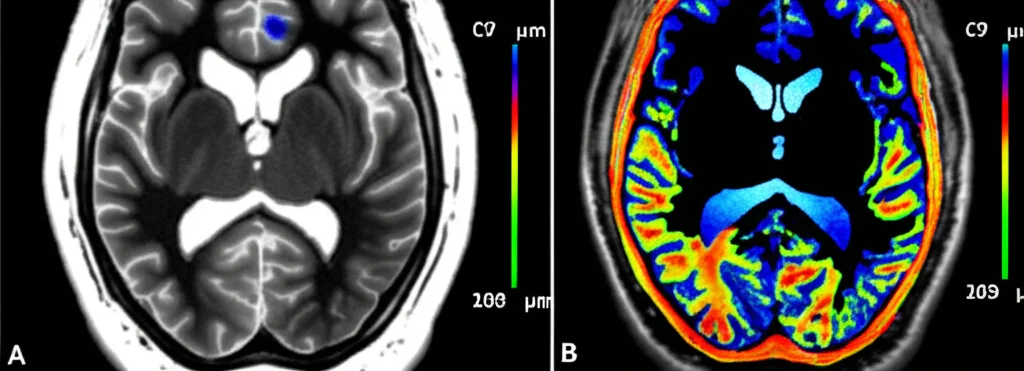

Il problema è che misurare solo il volume delle WMH potrebbe non dirci tutta la verità. È un po’ come giudicare la salute di una foresta contando solo gli alberi caduti, senza guardare lo stato di quelli ancora in piedi. Per fortuna, oggi abbiamo tecniche di neuroimaging più avanzate, come la mappatura quantitativa della suscettibilità (QSM). Questa tecnica ci permette di “guardare dentro” il tessuto cerebrale e ottenere informazioni sulla sua microstruttura, come l’integrità della mielina (la guaina protettiva dei neuroni) e la distribuzione del ferro. È un po’ come avere una lente d’ingrandimento super potente!

Combinando la misura del volume con l’analisi della suscettibilità delle WMH, potremmo capire molto meglio cosa sta succedendo a livello microscopico e magari identificare segni precoci di danno, prima ancora che il volume cambi significativamente.

- Le caratteristiche delle loro iperintensità della sostanza bianca (WMH): sia il volume totale che la suscettibilità media (usando la QSM).

Cosa significa una “minore suscettibilità”? La suscettibilità in QSM è influenzata dal ferro e dalla mielina. Una ridotta suscettibilità nelle WMH potrebbe indicare una perdita di ferro (magari dagli oligodendrociti, le cellule che producono mielina e sono ricche di ferro) o una perdita di mielina stessa, entrambi segni di danno microstrutturale.

Questo suggerisce che i cambiamenti microstrutturali nella sostanza bianca, rilevati dalla suscettibilità, potrebbero essere più sensibili e precoci nel riflettere l’influenza del plesso coroideo sulla progressione della malattia, rispetto ai cambiamenti volumetrici. La suscettibilità potrebbe essere un marker più dinamico!